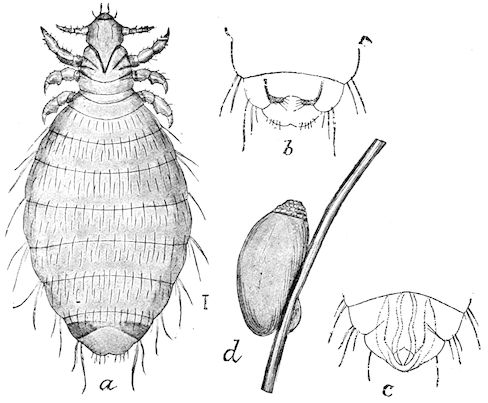

Fig. 2.—Horse suffering from osseous cachexia.

Fig. 3.—Pig suffering from osseous cachexia (fourth stage).

Fig. 4.—Deformity of the face in the horse shown in Fig. 2.

Fig. 5.—Head of a pig suffering from osseous cachexia.

Fig. 6.—Osseous cachexia. This condition developed in two months, the last month of gestation and the first of lactation.

Fig. 7.—Osseous cachexia: softening of the maxillæ.

Fig. 8.—Transverse section through the middle region of the face in a pig suffering from osseous cachexia.